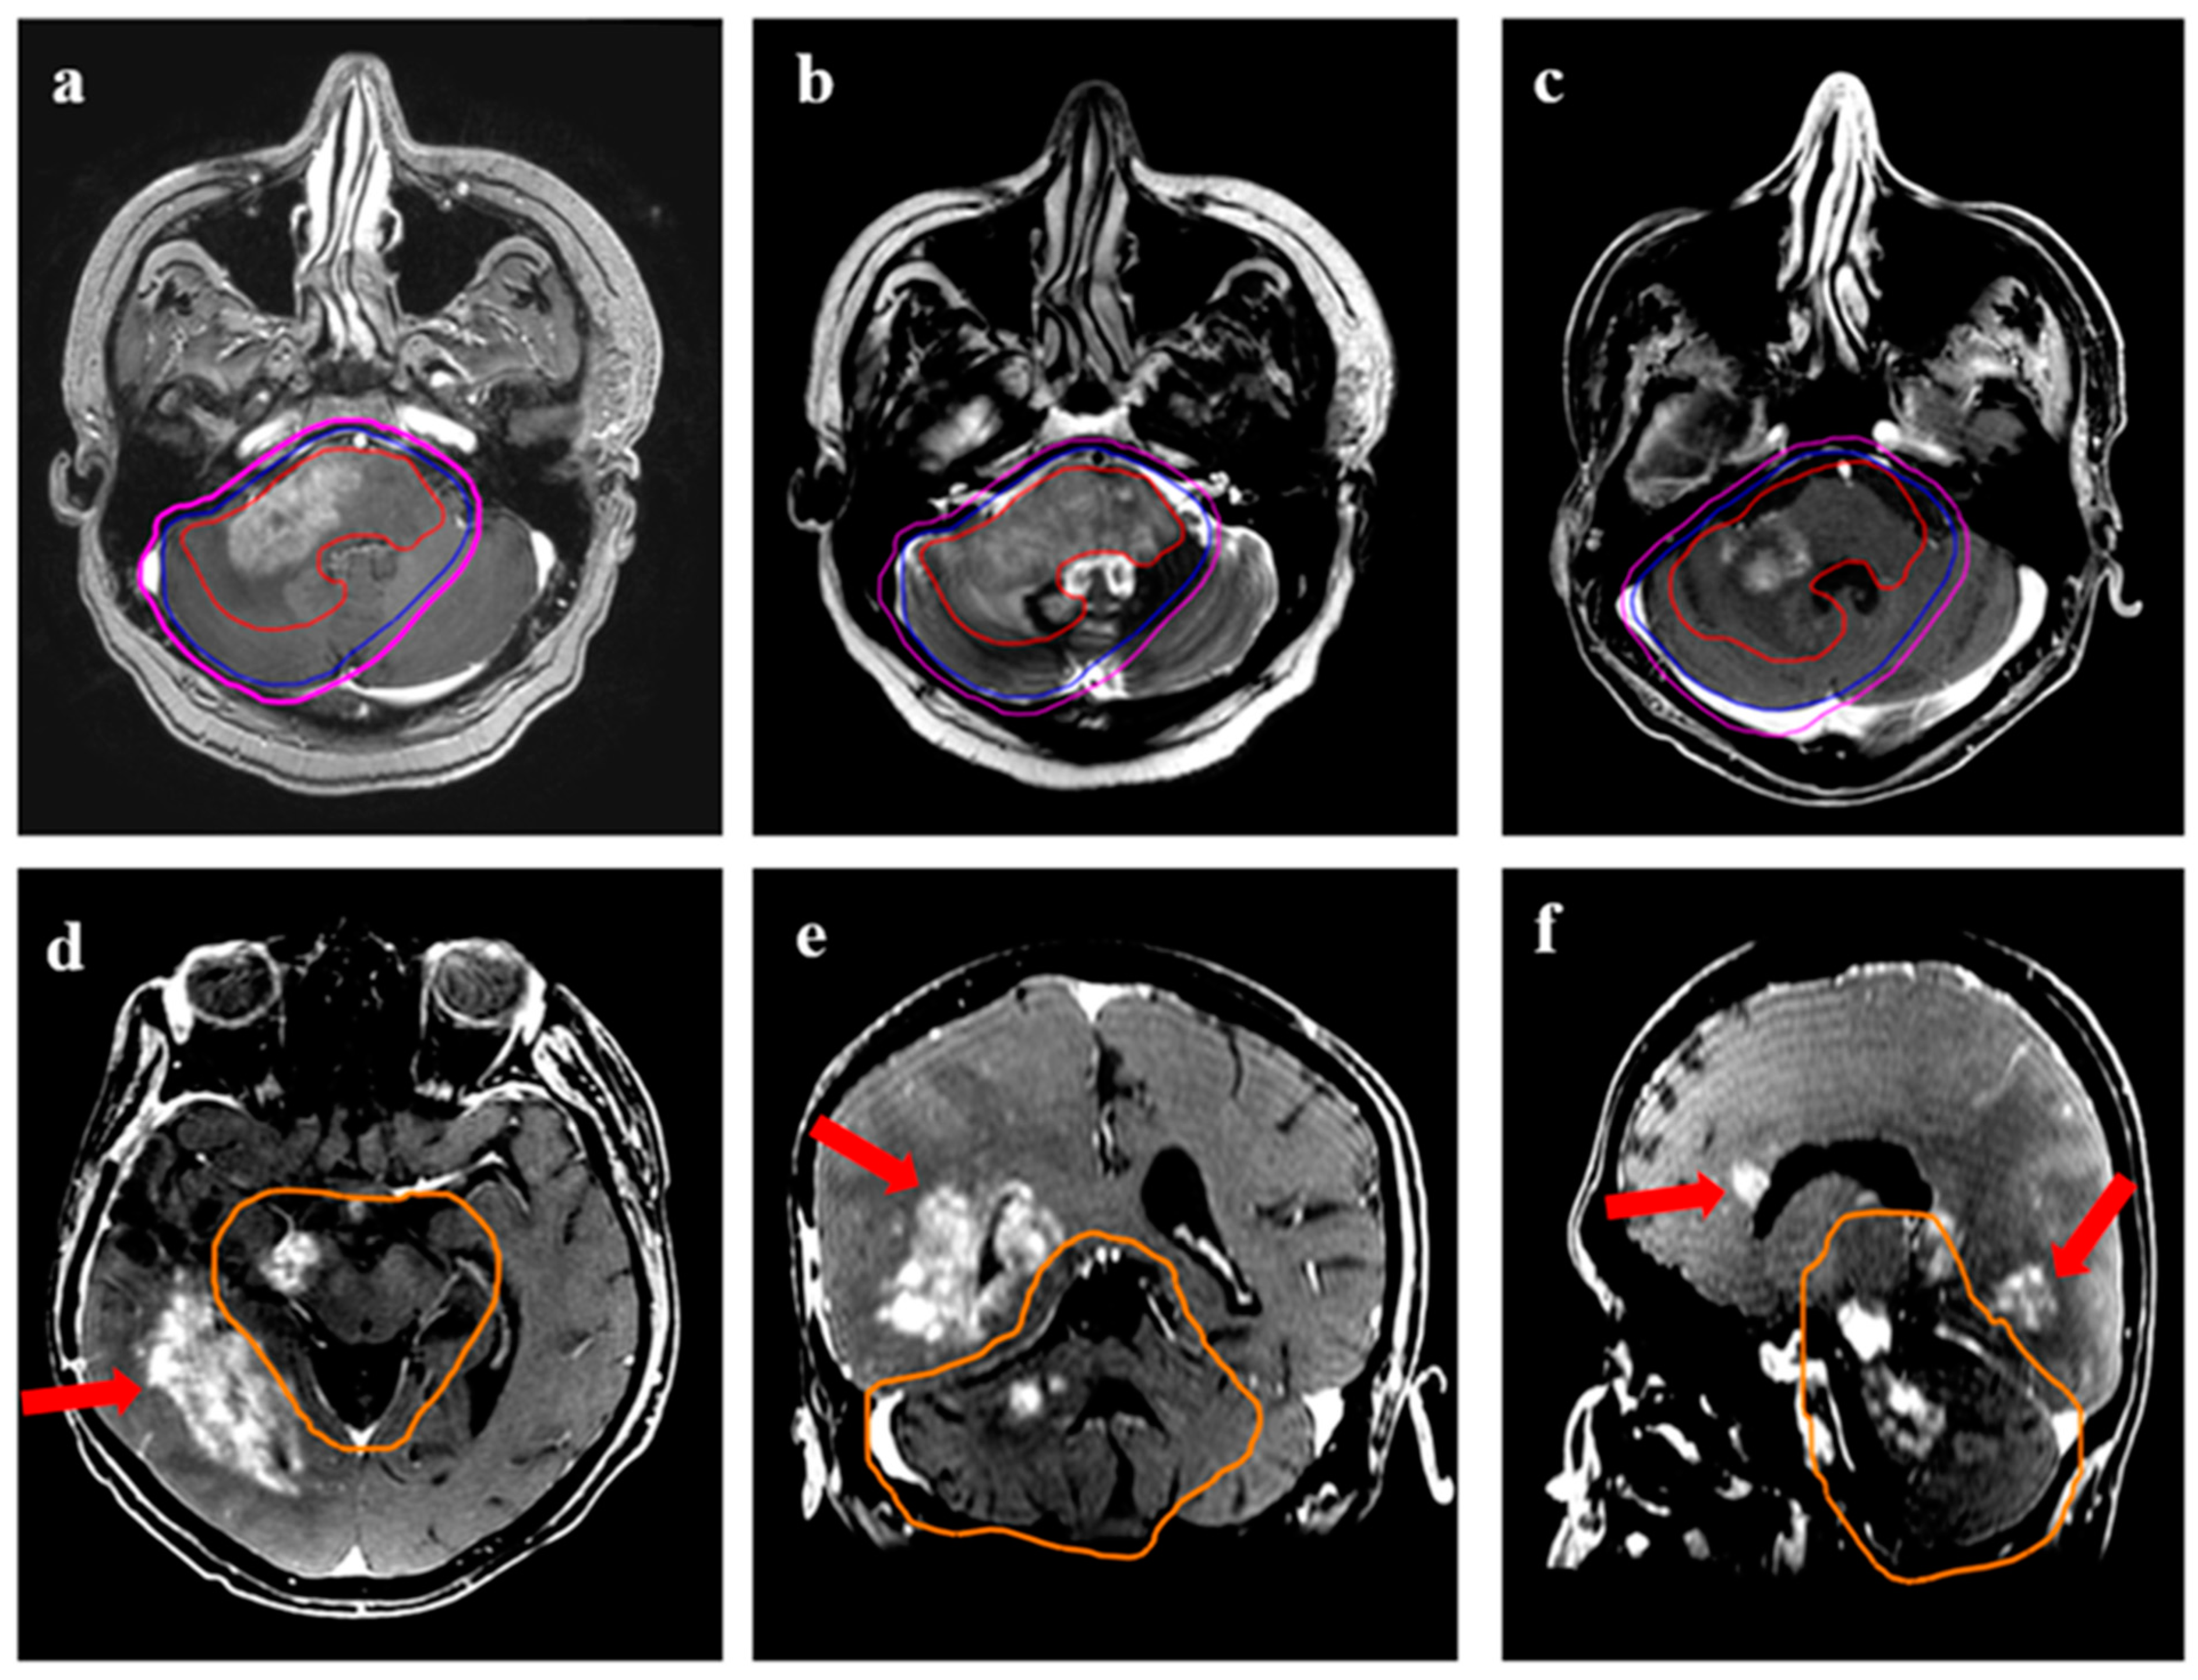

Figure 5.

Two patients with central recurrence, each in the upper and lower panel. (a) (37-year male with IDH-mutant astrocytoma) shows target volumes (GTV: red, CTV: blue; PTV: magenta) on T2-FLAIR MRI. The CTV was drawn to include all areas of T2w hyperintensity. (b,c) is T2-FLAIR and T1w contrast images showing recurrent disease (arrow) and its relation with the 95% isodose line (orange line). (d) (56-year male with recurrent glioblastoma) shows the target volumes for another patient volumes (GTV: red, CTV: blue; PTV: magenta) on T1w contrast MRI. The GTV was the enhancing disease, with CTV drawn as an expansion of 10 mm around the enhancing disease. (e,f) show the recurrence volumes with respect to target volumes and the 95% isodose line (orange), respectively. The major portion of recurrent disease can be seen lying within the 95% isodose line.

Figure 6.

Demonstration of marginal recurrence following re-irradiation for a 43-year female with transformed high-grade glioma. (a) shows the target volumes (GTV: red, CTV: blue; PTV: magenta) on T1w contrast MRI. The GTV was the enhancing disease, with CTV drawn as an expansion of 10 mm around the enhancing disease. (b,c) demonstrates recurrent disease (arrows) with respect to target volumes and 95% isodose line (orange), 1. (d) is a representation from lower axial slices showing the growth of recurrent disease further beyond the 95% isodose line.